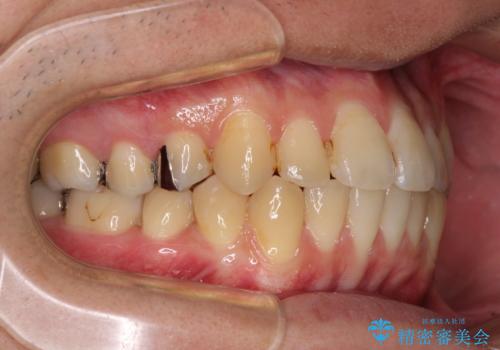

インビザラインによる前歯のクロスバイト改善におけるリスクとして、前歯歯髄充血・歯髄壊死が挙げられます。

ワイヤー矯正を併用する目的として、短期間でデコボコやクロスバイトを改善する他に、歯髄充血リスクを低減させるというものがあります。